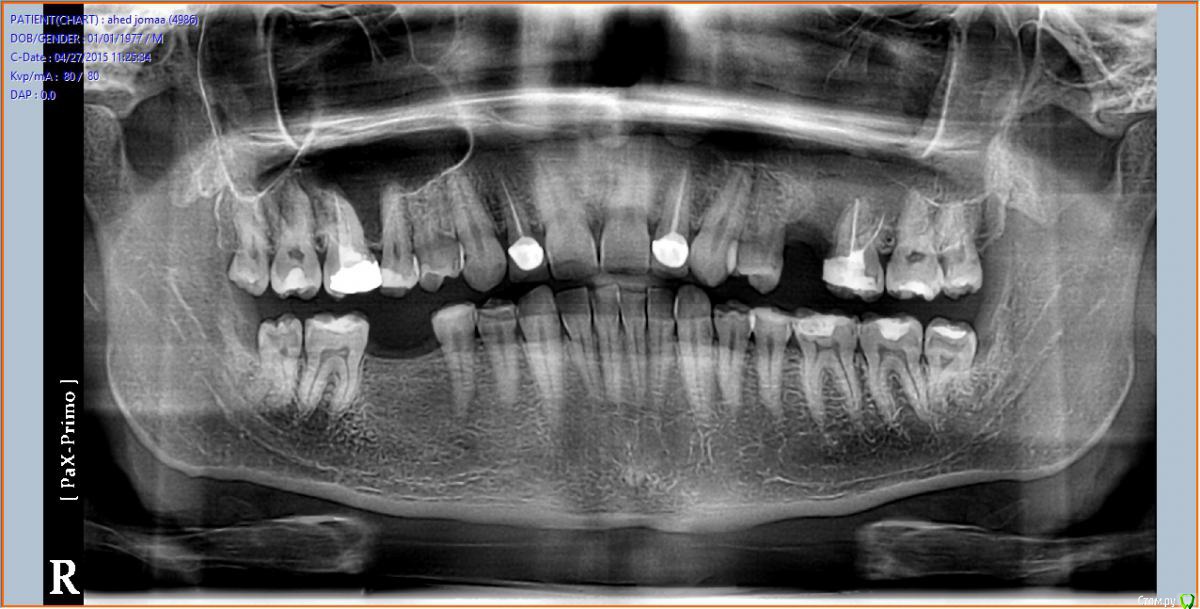

bilal Опубликовано 27 апреля, 2015 Поделиться Опубликовано 27 апреля, 2015 (изменено) добрый вечер.обратился пациент от другого врача. со слов пациента месяц назад удалил 25, обратился с жалобами на гноетечение из носа слева и сообщение с пазухой на месте удаления, по снимку видно что там корень от 25 остался в пазухе.вопрос: каким путем лучше достать через лунку и сообщение с пазухой или латерально как при открытом синус лифте, и сообщение лучшее закрыт сразу или оставить для промывание на пару дней.кт нет возможности делать .спасибо заранее Изменено 27 апреля, 2015 пользователем bilal Ссылка на комментарий

Kev Опубликовано 28 апреля, 2015 Поделиться Опубликовано 28 апреля, 2015 Ребята, что-то с телефона не могу рассмотреть где там корень в пахузе на ОПТГ, покажите. Ссылка на комментарий

bilal Опубликовано 28 апреля, 2015 Автор Поделиться Опубликовано 28 апреля, 2015 Вот, нарисовал границы пазухи и корень, как я вижу Ссылка на комментарий

Большой Зеленый Опубликовано 29 апреля, 2015 Поделиться Опубликовано 29 апреля, 2015 Что то не похоже на корень. 5 Ссылка на комментарий

Strelok96 Опубликовано 29 апреля, 2015 Поделиться Опубликовано 29 апреля, 2015 Тоже не вижу корень на снимке, надо делать КТ. 2 Ссылка на комментарий

alekszander Опубликовано 29 апреля, 2015 Поделиться Опубликовано 29 апреля, 2015 не стал бы я лезть без более тщательной R-диагностики, и скорее всего бы все же направил бы на эндоскоп.PS про корень который не видят, как-то постеснялся спросить, поскольку сколько не смотрю так и не вижу его. 1 Ссылка на комментарий

kriokov Опубликовано 30 апреля, 2015 Поделиться Опубликовано 30 апреля, 2015 Вот, нарисовал границы пазухи и корень, как я вижусделайте обычный прицельный снимок, если корень так низко как вы отметили-- будет видно. 2 2 Ссылка на комментарий